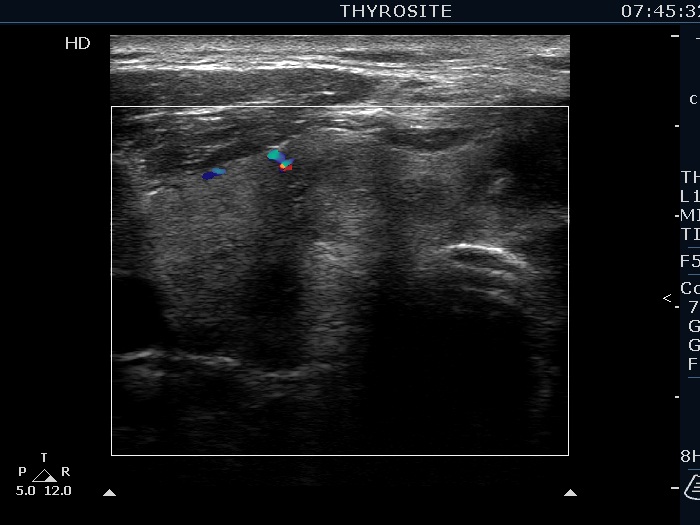

Ultrasonography. The right lobe was echonormal and presented several hypoechoic nodules. A large, inhomogeneous, partly deeply hypoechoic, partly minimally hypoechoic or echonormal mass occupied the left lobe. The borders of the tumor were irregular. There were multiple lymph nodules upper and lateral to the left thyroid lobe. The nodes had a heterogeneous pattern and lacked hilum. The vascularity was scanty both in the thyroid nodules and the lymph nodes.